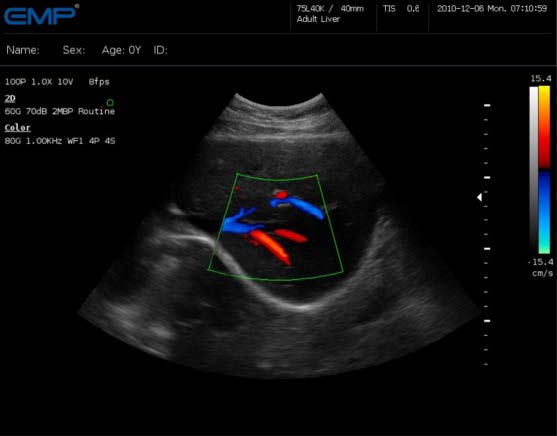

大家可以看到這幅圖的右邊跟左邊相比多了一些紅色和藍色。這就是所謂的“彩超”,它的原理就是“多普勒效應(yīng)”。運用多普勒效應(yīng)來探測紅細胞的運動,并將這些運動的方向用彩色表達出來,就形成了彩色血流圖。同時也可以測算出血流速度、阻力指數(shù)等參數(shù)。為了統(tǒng)一,我們一般將朝向探頭的血流標記為紅色,背離探頭的血流標記為藍色。這個是可以通過檢查者的習(xí)慣來調(diào)節(jié)的并不是一成不變的。

多普勒超聲目前可分為脈沖式多普勒、連續(xù)式多普勒、高脈沖重復(fù)頻率式多普勒、多點選通式多普勒以及彩色多普勒血流顯像五種,其中脈沖式多普勒應(yīng)用比較廣。它是在二維超聲心動圖定位情況下,利用多普勒原理,采用一系列電子技術(shù),實時顯示心臟或大血管內(nèi)某一點一定容積血流的頻譜圖。是一種無創(chuàng)傷性能檢查出心內(nèi)分流和返流的技術(shù)。連續(xù)式多普勒可連續(xù)發(fā)射沖波,因此具有測量高速血流的能力,對于定量分析心血管系統(tǒng)中的狹窄、返流和分流性病變,有其明顯的優(yōu)點。